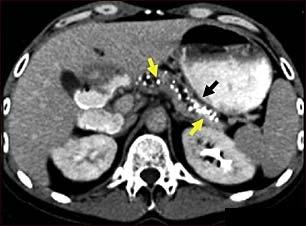

Pancreatita cronica (Inflamatia cronica a pancreasului)